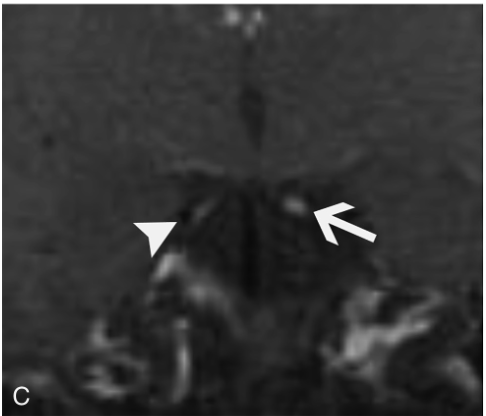

画像所見

画像所見としては,脳神経の造影効果and/or腫大を呈する.

神経サルコイドーシスやリンパ腫,癌性髄膜炎は,他の部位の結節状の造影効果を生じやすい.

CIDPは造影効果の伴わない神経根の腫大を呈する.薄いスライスでの脳MRIは,脳神経の評価や造影効果のパターンを評価するのに特に有用である.